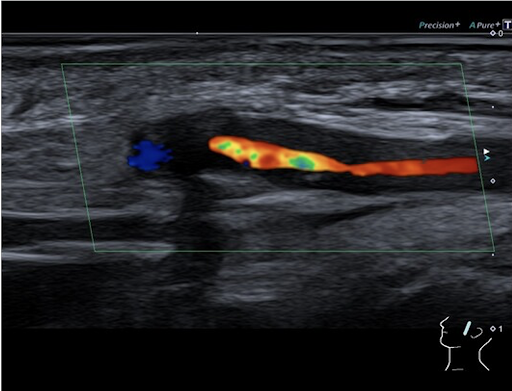

Color Doppler sonography of the left temple: Significant inflammatory changes and swelling of the temporal artery wall with severe stenosis of the vessel lumen.

RZA.png